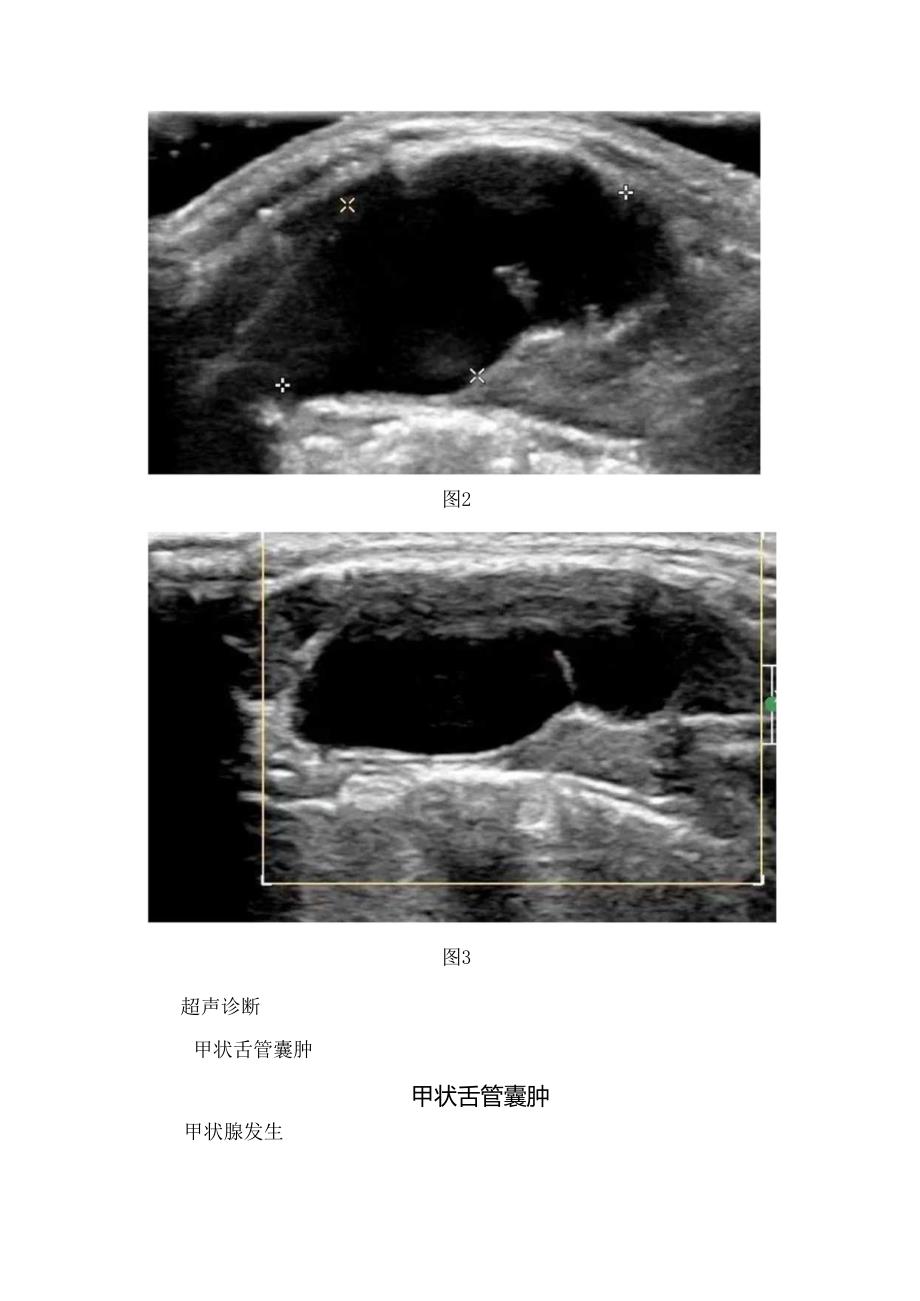

临床甲状舌管囊肿病例、发生原因、临床表现、超声表现、鉴别诊断及治疗措施病例患儿,男性,14岁,发现颈部包块2年余。体格检查颈前稍偏左触及2lcm包块,质软,活动度可,无压痛,无明显搏动。超声所见颈前稍偏左甲状舌骨水平探及囊性回声,形态欠规则,内透声差,内无血流信号,囊壁未见明显血流信号。(图1-3)图1图2图3超声诊断甲状舌管囊肿甲状舌管囊肿甲状腺发生第4周初,在原始咽底壁正中线处(相当于第1对咽囊平面),内胚层细胞增生,向间充质内下陷形成一盲管,称甲状舌管,即甲状腺原基。它沿颈部正中向尾端方向生长、延伸,末端向两侧膨大,形成甲状腺的侧叶。第7周时、甲状舌管的上段退化消失,仅在起始处残留一浅凹,称舌盲孔。临床表现甲状舌骨囊肿表现为颈部正中或略偏囊性结节,质软,边界清,无压痛。部分可随吞咽动作而上下移动,发生感染时,则会有红肿热痛的表现。超声表现颈部正中线或略偏无回声包块,舌骨上下多见。多为类圆形,边界清,内部回声多样,CDFI:无血流信号。囊肿继发感染时,囊内透声差,囊壁增厚并可见血流信号。鉴别诊断鲤裂囊肿:多位于颈动脉三角区,肿物多偏离中线,不随吞咽而活动,与舌骨无关。淋巴管瘤:多发生于儿童,多位于颈后三角区,可单房或多房,呈分隔状,有向周围组织间隙生长的特点。治疗手术切除。有继发感染者应先控制感染,再择期手术。